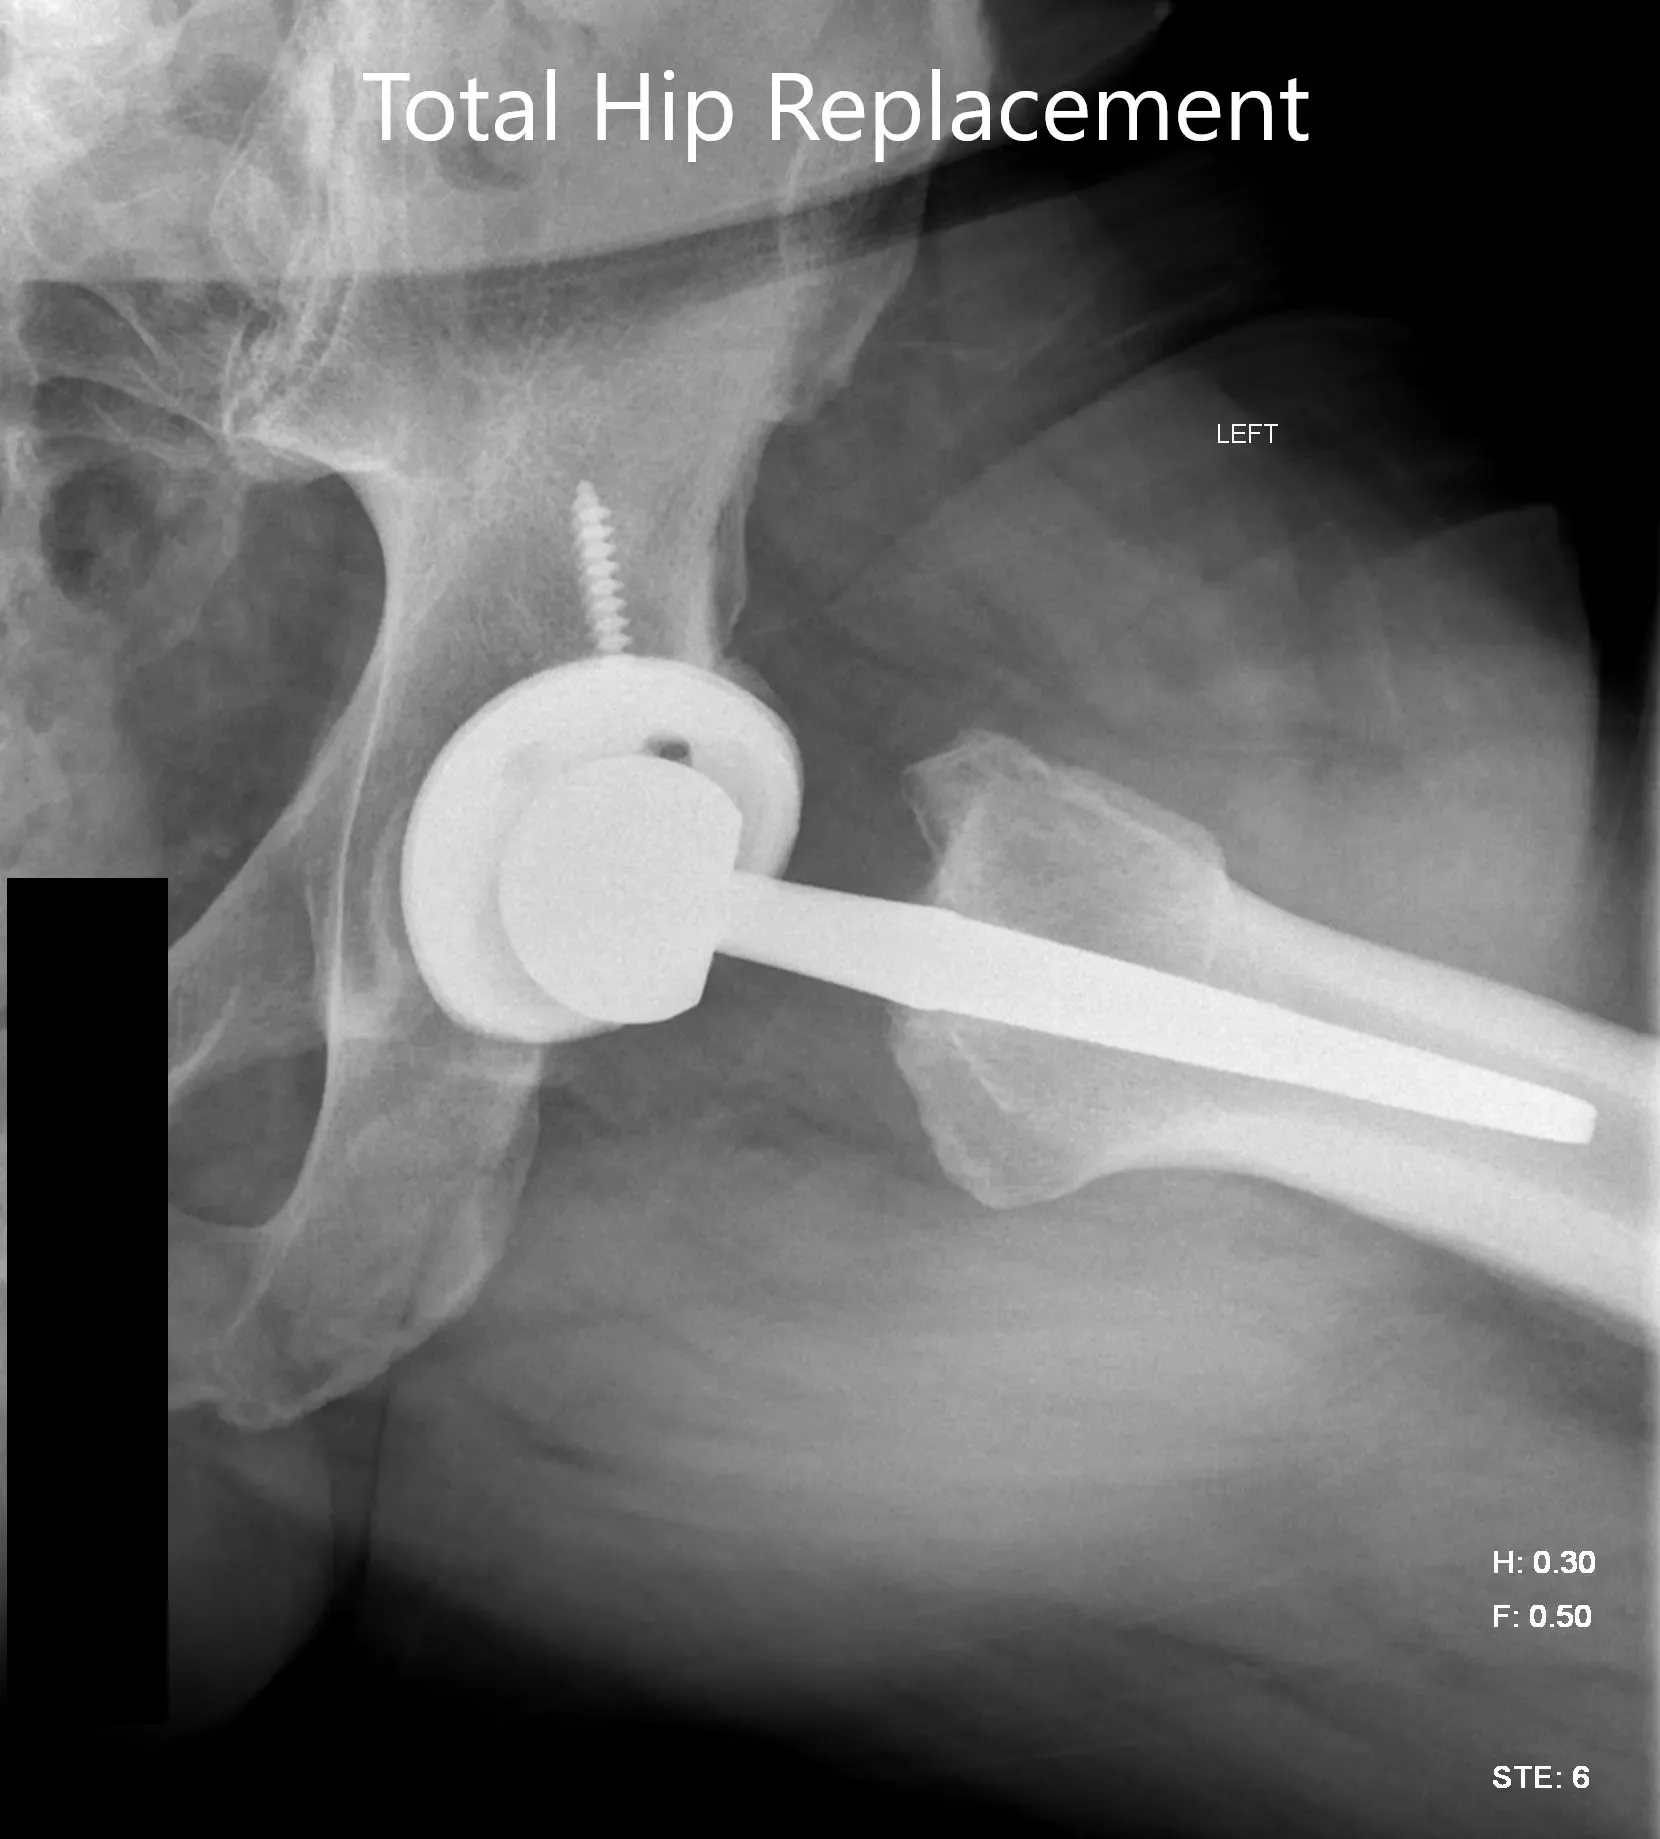

Imágenes de radiografías postoperatorias que muestran la vista AP y la vista lateral con patas de rana.